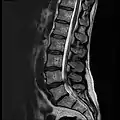

MRI lumbar spine with degeneration (sagittal FAST STIR)- MRI lumbar spine pre-hemilaminectomy (sagittal T2 FRFSE)